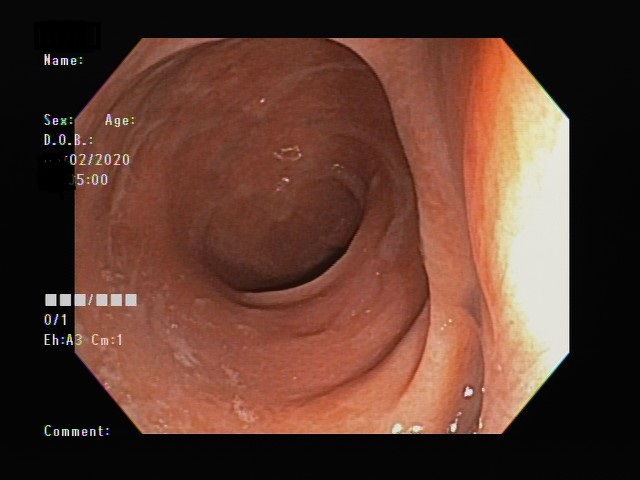

我們再來看看另一位 70 歲的阿嬤,這是大腸鏡下的照片,完全看不出直腸有任何異狀。

可是偏偏在觸診時,怎麼摸都覺得直腸有一個腫塊,經過轉診,最後確診為直腸基質瘤,是一種罕見的直腸惡性腫瘤。